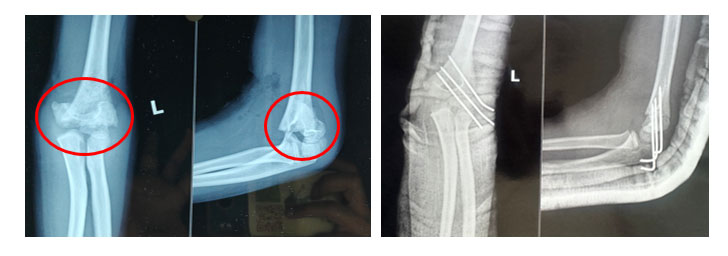

Elbow Supracondylar Humerus Fracture